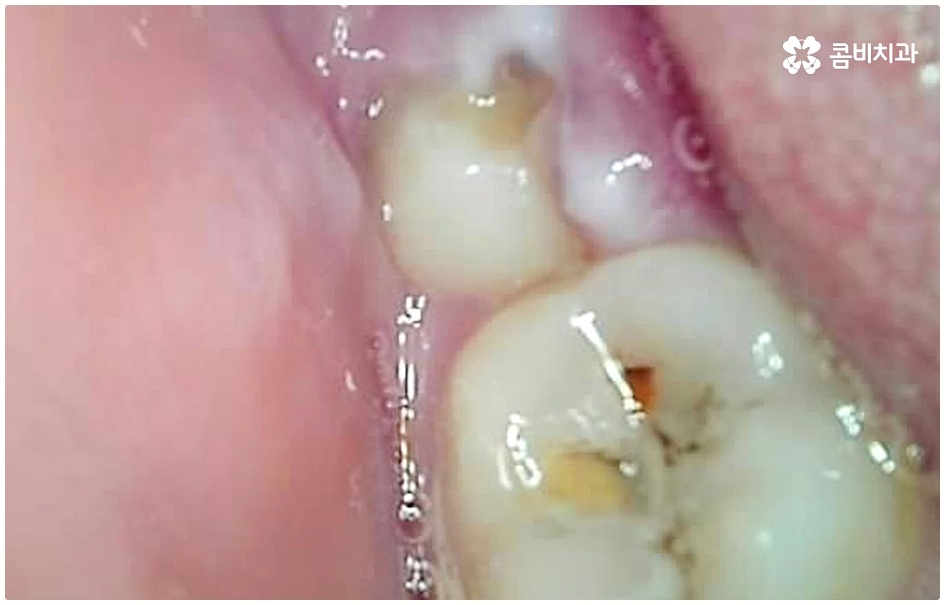

이 때 교합면, 즉 치아의 씹는 면이 아닌 치아 사이 충치가 생겼다면 쉽게 발견하기도 어렵고 치료를 위한 접근 역시 까다롭기 때문에 주의하실 필요가 있습니다. 물론 가장 흔하게 발생하는 것은 넓고 홈이 파여 있으며 직접 음식물을 저작하는 교합면에 생기는 충치일 것이나 음식물 찌꺼기가 끼기 쉽고 세균이 서식하기도 쉬우며 양치질을 하더라도 칫솔모가 잘 닿지 않기 때문에 관리가 어려운 치아 사이 좁은 틈새에도 역시 충치가 잘 생길 수 있는 거예요.

치아 사이 충치는 치아끼리 맞닿아 있는 부분이라 노출이 잘 되지 않기 때문에 육안으로 식별이 어려운 경우가 많은데, 만약 눈으로 확인될 정도라면 질환이 이미 많이 진행한 상태이므로 명동치과 에서 빠른 치료를 받아주실 필요가 있어요.

치아의 구조를 살펴보면 겉표면인 단단한 법랑질은 교합면에서 가장 두껍고 잇몸쪽으로 갈수록 얇아지기 때문에 치아 사이의 인접면은 치아의 신경과 한층 가까워서 충치가 조금만 진행되어도 신경치료를 받아야 할 수 있으며 인접면 충치가 심하여 레진이나 인레이 수복으로 치아의 외형을 재현하기 어려운 경우에는 치아 전체를 다듬어 씌우는 명동치과 크라운 치료를 해줘야 하니 부담이 커지기 전에 치료 시기를 놓치지 않도록 주의하시는 게 좋을 거예요.

인접면 충치는 일반적으로 양치를 꼼꼼히 하기 어려운 아동에게 많이 발생하지만, 식습관이나 구강위생 관리 소홀 등을 이유로 성인에게도 빈번히 발생하는 질환이며 발견과 치료에 있어 일반적인 충치보다 어려움이 크기 때문에 주기적인 명동치과 검진 및 스케일링 처치, 그리고 치실 사용 등 꼼꼼한 양치질 등을 통해 초기 대처 및 예방을 해주는 것이 매우 중요하다고 할 수 있습니다.